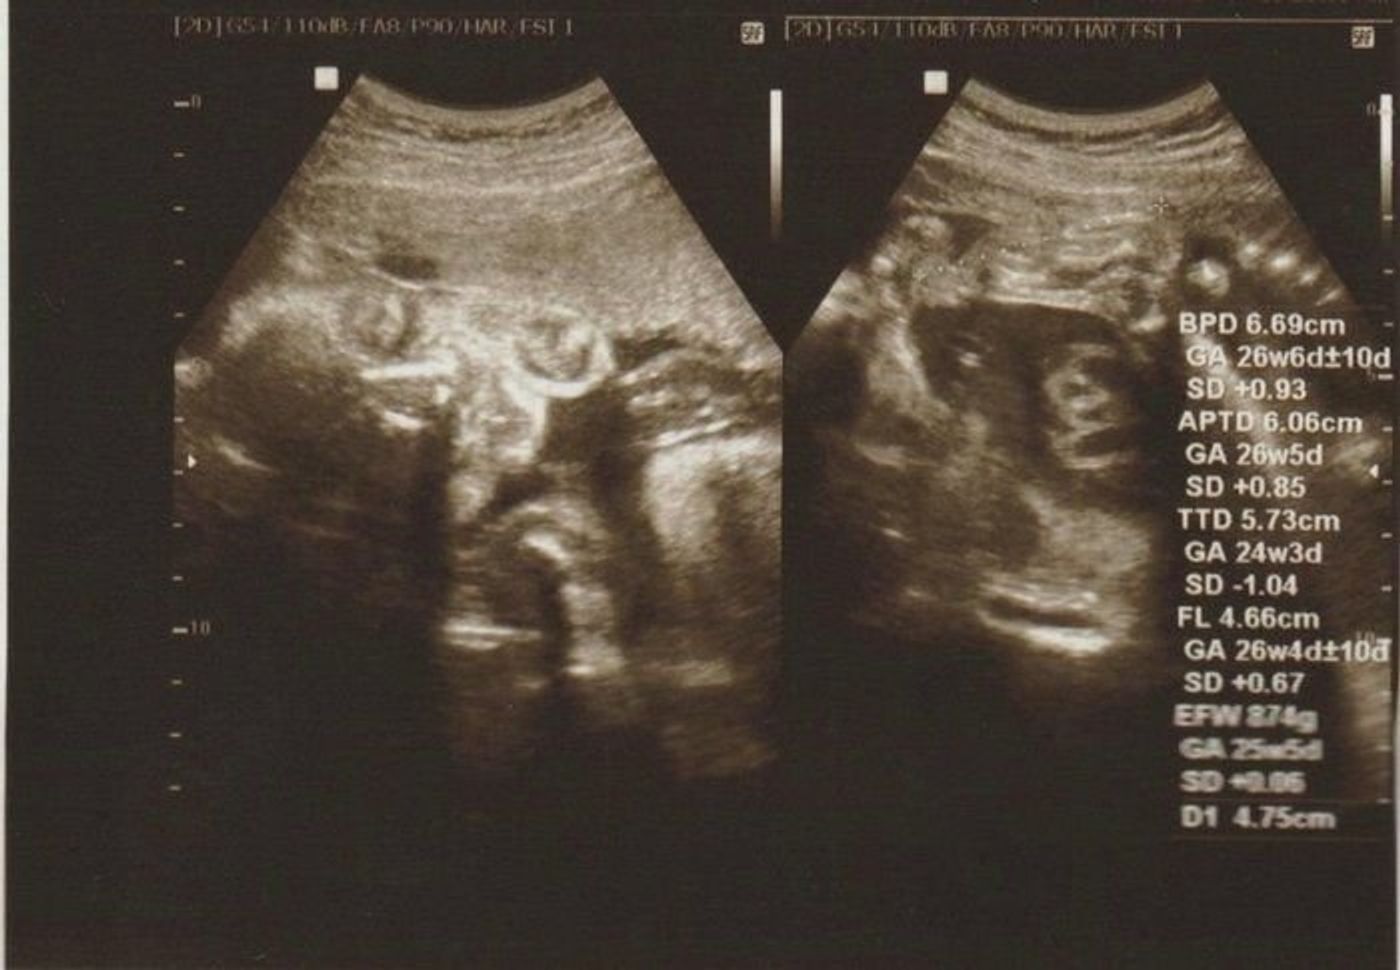

妊娠24週、25週、26週、27週に気になる胎児のこと、ママのこと。 赤ちゃんは頭位でいることが多いのですが、くるくる動いているうちに骨盤位になることもあります。 妊娠25週0日の胎児妊娠25週は妊娠7ヶ月の2週目。 妊娠中期も残すところあと3週間です。 妊娠25週のお腹の赤ちゃん-指しゃぶりやまばたき 妊娠25週、お腹の赤ちゃんの体重は約750gに成長し、子宮の中でくる

25週目 赤ちゃん 体重- 妊娠25週頃になると、胎児の体重は 600~1150gほど に成長します。 赤ちゃんの大脳皮質が発達するようになり、神経細胞もが細やかになるので、ストレスを与えるような行為は避妊娠25週 胎児の体重 感情も徐々に発達するように 妊娠25週胎児体重は正常発育児の954%が 546g~996g 平均体重: 771g となります。 ※1 25週目の赤ちゃんは、既に海馬が発達しているの

これは先ほど説明した 胎児の推定体重を、「胎児発育曲線」グラフに当てはめて判断しています。 胎児発育曲線グラフとは、正期産(37週~41週のお産)で生まれた 正常な体重の赤ちゃんの胎児時 全身麻酔で、目が覚めたときには病室でした。 妊娠25週と6日、産まれたのは870グラムの小さな男の子。 我が子に会えたのは出産してから半日以上経ってから でした。 nicuの保育器体脂肪率と体重は? 10月16日の体脂肪率は237%でした。 前回報告時が246%でしたので、09%の低下でした。 22%台から25%台で変動していて、ボラティリティの高いままです。 10月16日の

妊娠25週目 胎児の様子 この頃の赤ちゃんは約 身長32㎝・体重650~900g になります!! どんどん成長していってくれていますね♡ 妊娠25週目の エコー動画 を見つけたのでよ 妊娠25週目ママは体重増加に要注意。 赤ちゃんは呼吸の練習をスタート! 妊娠25週目になり、ママのお腹はずいぶん大きくなっているでしょう。 お腹が大きく